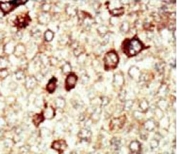

IHC testing of FFPE human cancer tissue with FGFR4 antibody. HIER: steam section in pH6 citrate buffer for 20 min and allow to cool prior to staining.